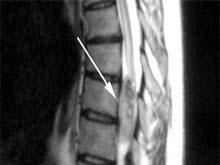

磁共振成像是一种较理想的检查方法,无电离辐射的副作用,可三维观察脊髓像,能显示肿瘤组织与正常组织的界线、肿瘤的部位、大小和范围,并直接把肿瘤勾划出来,显示其纵向及横向扩展情况和与周围组织结构的关系,已成为脊髓肿瘤诊断的首选方法。MRI对于区别髓内、髓外肿瘤更有其优越性。髓内肿瘤的MRI成像,可见该部脊髓扩大,在不同脉冲序列,肿瘤显示出不同信号强度,可与脊髓空洞症进行鉴别。髓外肿瘤可根据其与硬脊膜的关系进行定位,准确率高。

MRI矢状面成像可见肿瘤呈边界清楚的长T1、长T2信号区,但以长T1为主,有明显增强效应,有的呈囊性变。轴位像显示颈脊髓被挤压至一侧,肿瘤呈椭圆形或新月形。对于经椎间孔向外突出的哑铃形肿瘤,可见椎管内、外肿块的延续性。由于MRI直接进行矢状面成像,检查脊髓范围比CT扫描大,这是CT所无法比拟的,而且于MRI可以显示出肿瘤的大小、位置、及组织密度等,特别是顺磁性造影剂Gd-DTPA的应用可清楚显示肿瘤的轮廓,所以MRI对确诊和手术定位都是非常重要的,这方面CT或CTM远不如MRI。

颈椎管内肿瘤不同于颈椎病的鉴别点: 1.颈椎斜位平片椎间孔扩大或椎板骨质变薄,可支持髓外神经鞘瘤的诊断; 2.颈脊髓椎管造影,尤其是经小脑延髓池注药造影容易确诊; 3.颈脊髓的MRI检查:矢状面常可见到边缘清楚的长T1及长T2加权信号,有明显的增强效应的肿瘤影。常伴有肿瘤中央长T1及长T2加权混杂信号,而轴位可见偏心形和新月形的肿瘤影并将脊髓挤到一侧。在T1加权像上,肿瘤的信号比脊髓弱;在T2加权像上,脊髓的信号略强于脊髓信号; 4.椎管内肿瘤患者脑脊液的蛋白定量大于2g/L。 脊髓蛛网膜炎 发生于颈椎者较少见常有感染及外伤史,症状呈波动性,多样性且不规则,脊髓造影呈典型的斑片状分布。